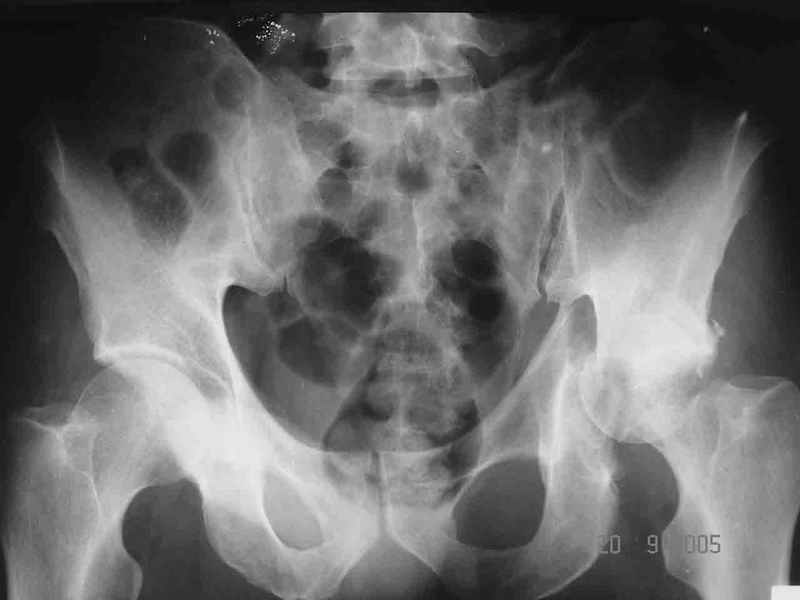

Больной 18 мая 2003 года в автоаварии получил перелом левой вертлужной впадины, вывих бедра. Госпитализирован в один из стационаров области.Вывих вправлен. В последствии бедро вывихивалось еще дважды. На консультацию был представлен снимок от 19.05.03г., больной переведен к нам 3.06.03г. Снимок при поступлении - перелом впадины, задне-верхний вывих бедра. 05.06.2003 г. выполнено открытое вправление вывиха левого бедра и остеосинтез стенки вертлужной впадины двумя винтами. Послеоперационный период без осложнений. Объем движений в левом тазобедренном суставе восстановился полностью. Выписан на амбулаторное лечение в удовлетворительном состоянии с рекомендациями 3 месяца ходить на костылях без нагрузки на оперированную конечность. На контрольных рентгенограммах левого тазобедренного сустава 13.10.2003 г. - признаки консолидации перелома; плотность, форма головки и состояние суставных поверхностей удовлетворительные. Разрешена дозированная осевая нагрузка, на конечность с использованием дополнительной опоры. 19.12.2003 г. больной обратился с жалобами на боли в левом тазобедренном суставе. На рентгенограммах левого тазобедренного сустава 19.12.2003 г., 20.02.04г. - асептичекий некроз головки бедра. 5.04.04г. - эндопротез. Сейчас ходит без трости, не хромает. Особенность эндопротезирования - при удалении винтов прослежена линия перелома заднего края впадины и предложено установить чашку несколько меньшего диаметра, чтобы она была покрыта несломанной частью.

Случай, представленный Вами, совсем не идентичен обсуждаемому. У Вашего пациента был поперечный перелом с переломом заднего края, а в обсуждаемом случае - высокий двухколонный перелом вертлужной впадины.

То есть в представленном Вами случае был перелом заднего типа, в нашем случае центрального. У Вашего больного был застарелый задний вывих, у нашего - перелом шейки. Столь раннее разрушение головки, вероятно, было во многом обусловлено тем, что не была достигнута анатомическая репозиция, головка бедра осталась смещенной кзади, что является частой ошибкой при крупных фрагментах свода.